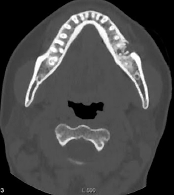

図❸ CT画像。6頬側皮質骨に骨吸収像がみられる

画像所見:パノラマX線画像では、6の根尖部分に大きさ約17×9mmのX線透過像を認める。CT画像では、6の根尖部分に頬側および舌側皮質骨に一部骨欠損を有し、大きさ約13×11×11mmの境界明瞭な透過像を認める(図❸)。